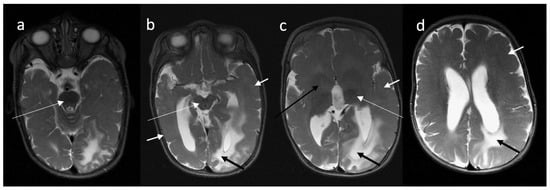

3.1. Clinical and Pathology Report